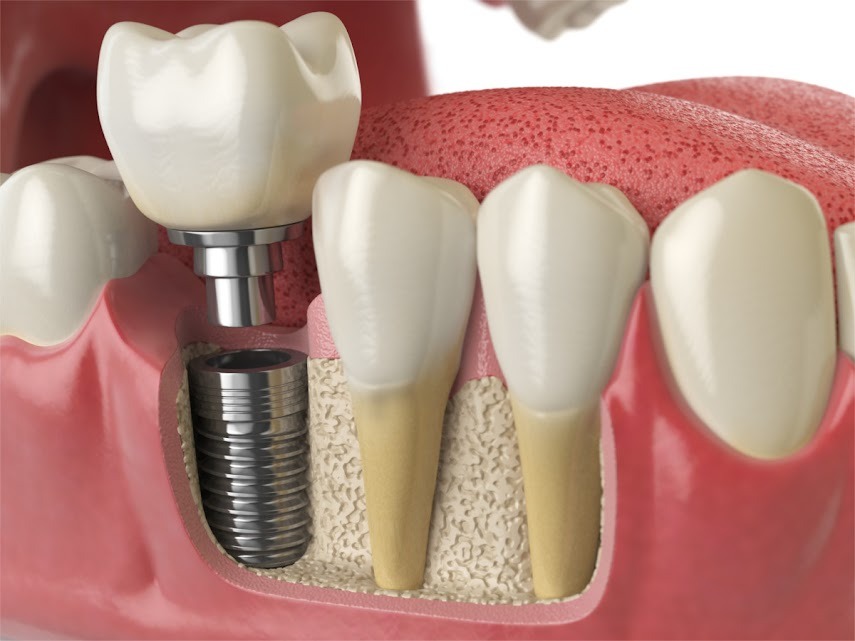

Single Tooth Implants

Missing a single tooth? A dental implant is a permanent and natural-looking solution. This procedure involves placing a titanium post into the jawbone, which acts as a secure foundation for a custom-made crown.

- Restores function and aesthetics of your smile.

- Durable and long-lasting tooth replacement.

Prevents bone loss and maintains facial structure.